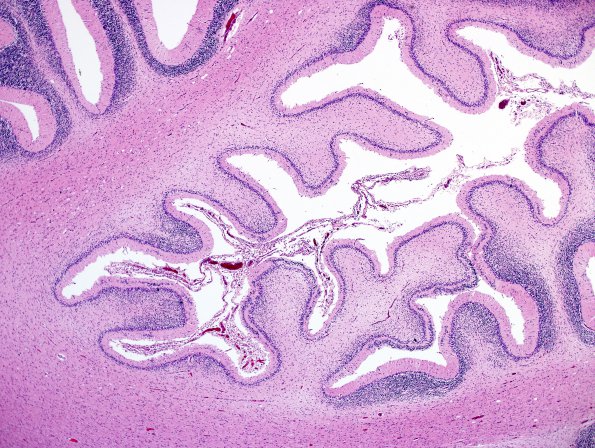

Close-up of focal cerebellar atrophy near the horizontal fissure (H&E)